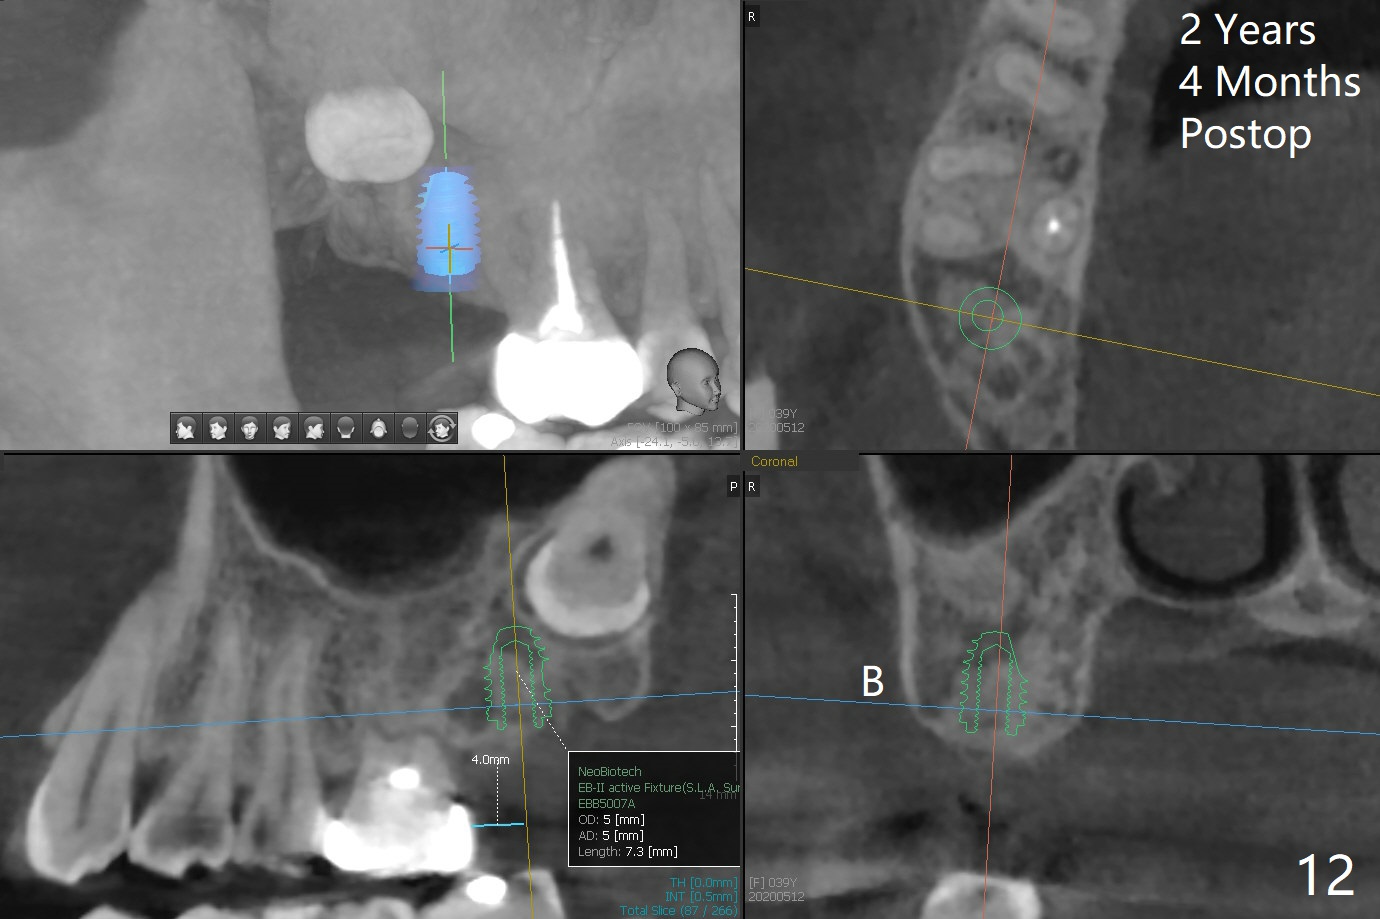

The socket of #2 heals 13 days postop; it appears that the bone graft remains in place (Fig.7,8 *). The patient is instructed to return in 3-4 months for impression and CT for guide. The socket heals 4 months postop (Fig.9,10). She plans to have implant next year, since she wants to add another insurance. The patient returns for implant without removal of the third molar 2 years 4 months post socket preservation (Fig.11). A 5x7.3 mm implant can be placed without invading the sac of the impacted third molar (Fig.12). In fact the lab has a better plan. A lump of bone forms in the previous socket 1 year 4 months postop (Fig.13 *). The ridge is wide and dense (Fig.14). A narrow implant placed oblique could be longer (Fig.15), as compared to a wide, short one (Fig.12).